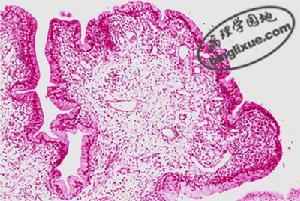

感染性肉芽腫(infective granuloma):由生物病原體如結核桿菌、傷寒桿菌、麻風桿菌、梅毒螺鏇體、黴菌和寄生蟲等引起。能形成具有特殊結構的細胞結節。例如:結核性肉芽腫(結核結節)主要由上皮樣細胞和一個或幾個郎罕斯(Langhans)巨細胞組成(圖1);傷寒肉芽腫(傷寒小結) 主要由傷寒細胞組成。

圖1結核性肉芽腫異物性肉芽腫(foreign body granuloma):由外科縫線、粉塵、滑石粉、木刺等異物引起。病變以異物為中心,圍以數量不等的巨噬細胞、異物巨細胞、纖維母細胞和淋巴細胞等,形成結節狀病灶。

(2)肉芽腫的組成成分 以典型的結核結節為例,結核性肉芽腫中心部為乾酪樣壞死,壞死灶周圍可見大量上皮樣細胞和郎罕斯多核巨細胞,外層淋巴細胞浸潤,周邊有纖維母細胞和膠原纖維分布。其中上皮樣細胞是結核性肉芽腫中最重要的成份。

炎性息肉(inflammatory polyp) 是在致炎因子長期作用下,局部黏膜上皮和腺體及肉芽組織增生而形成的突出於黏膜表面的肉芽腫塊。常見於鼻黏膜和宮頸。炎性息肉大小不等,從數毫米至數厘米,基底部常有蒂,鏡下可見黏膜上皮、腺體和肉芽組織明顯增生,並有數量不等的淋巴細胞和漿細胞浸潤(圖2)。